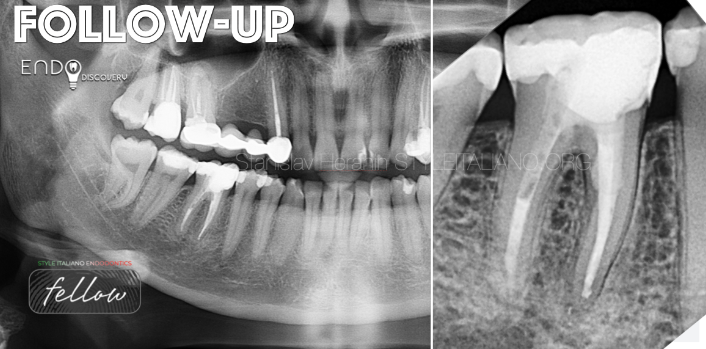

上图1:一名32岁患者因需根管再治疗转诊至我科

患者自述既往有多次根管治疗史。46牙存在旧的MOD复合树脂充填体破损。颊侧可见瘘管。诊断性X线片显示46牙根尖及根分叉区域透射影(怀疑穿孔)。叩诊无痛,牙周探诊在正常范围内。治疗计划为使用MTA进行非手术根管再治疗并修复穿孔。

初诊影像:全景X线片转诊患者:V.,32岁,女性诊断:46慢性根尖周炎根分叉穿孔 瘘管